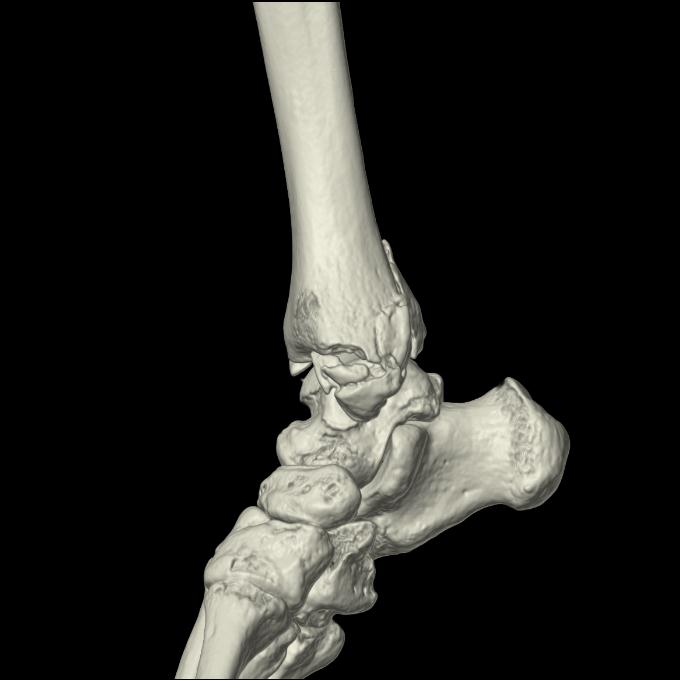

56476 8/28 4R 1/21 2R 左足関節 デジカメ写真 72歳女性 右足関節AS